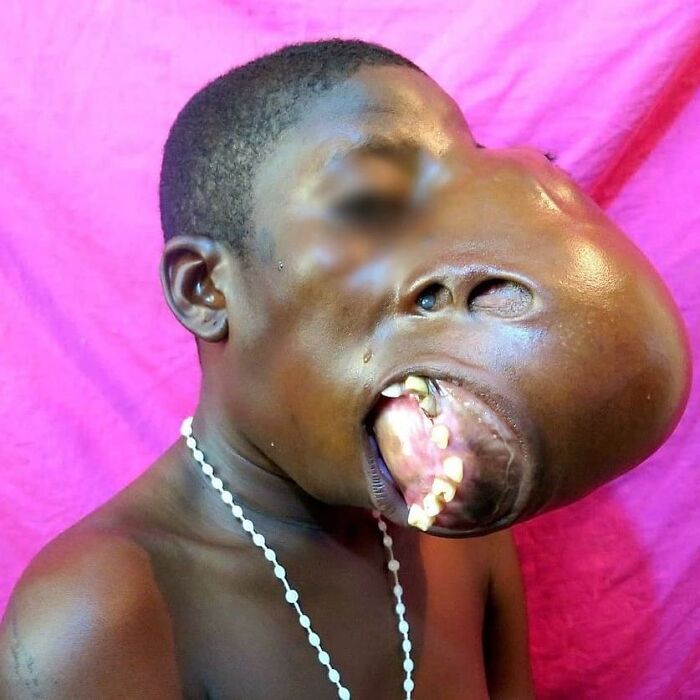

Extreme Case Of Craniofacial Fibrous Dysplasia

Craniofacial fibrous dysplasia is a bone disease of the face and skull that replaces normal bone with fibrous-type tissue. This tissue is not as hard as normal bone, and because it is soft and stringy, and as these areas of fibrous tissue grow and expand over time, it makes the bone more fragile, prone to break, and eventually become deformed. Craniofacial fibrous dysplasia may cause shifting of facial features and facial asymmetry, such as incorrect placement of the eyes, misalignment of the jaw, and other problems. It may appear in childhood, usually between the ages of 3 and 15. Boys are more often affected. Surgical treatment is usually required. Most cases of craniofacial fibrous dysplasia manifest as swellings that cause facial deformity and surgical recontouring after cessation of growth seems to provide the best results.